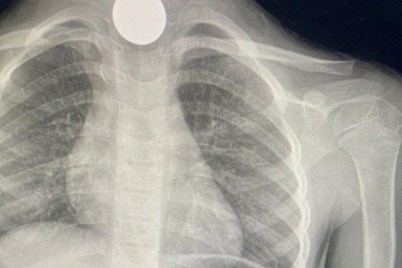

جدة - ريفان هوساوي تمكن فريق طبي متخصص بعلاج أمراض المسالك البولية من إنهاء معاناة مريض استمرت 3 سنوات بإستخراج...